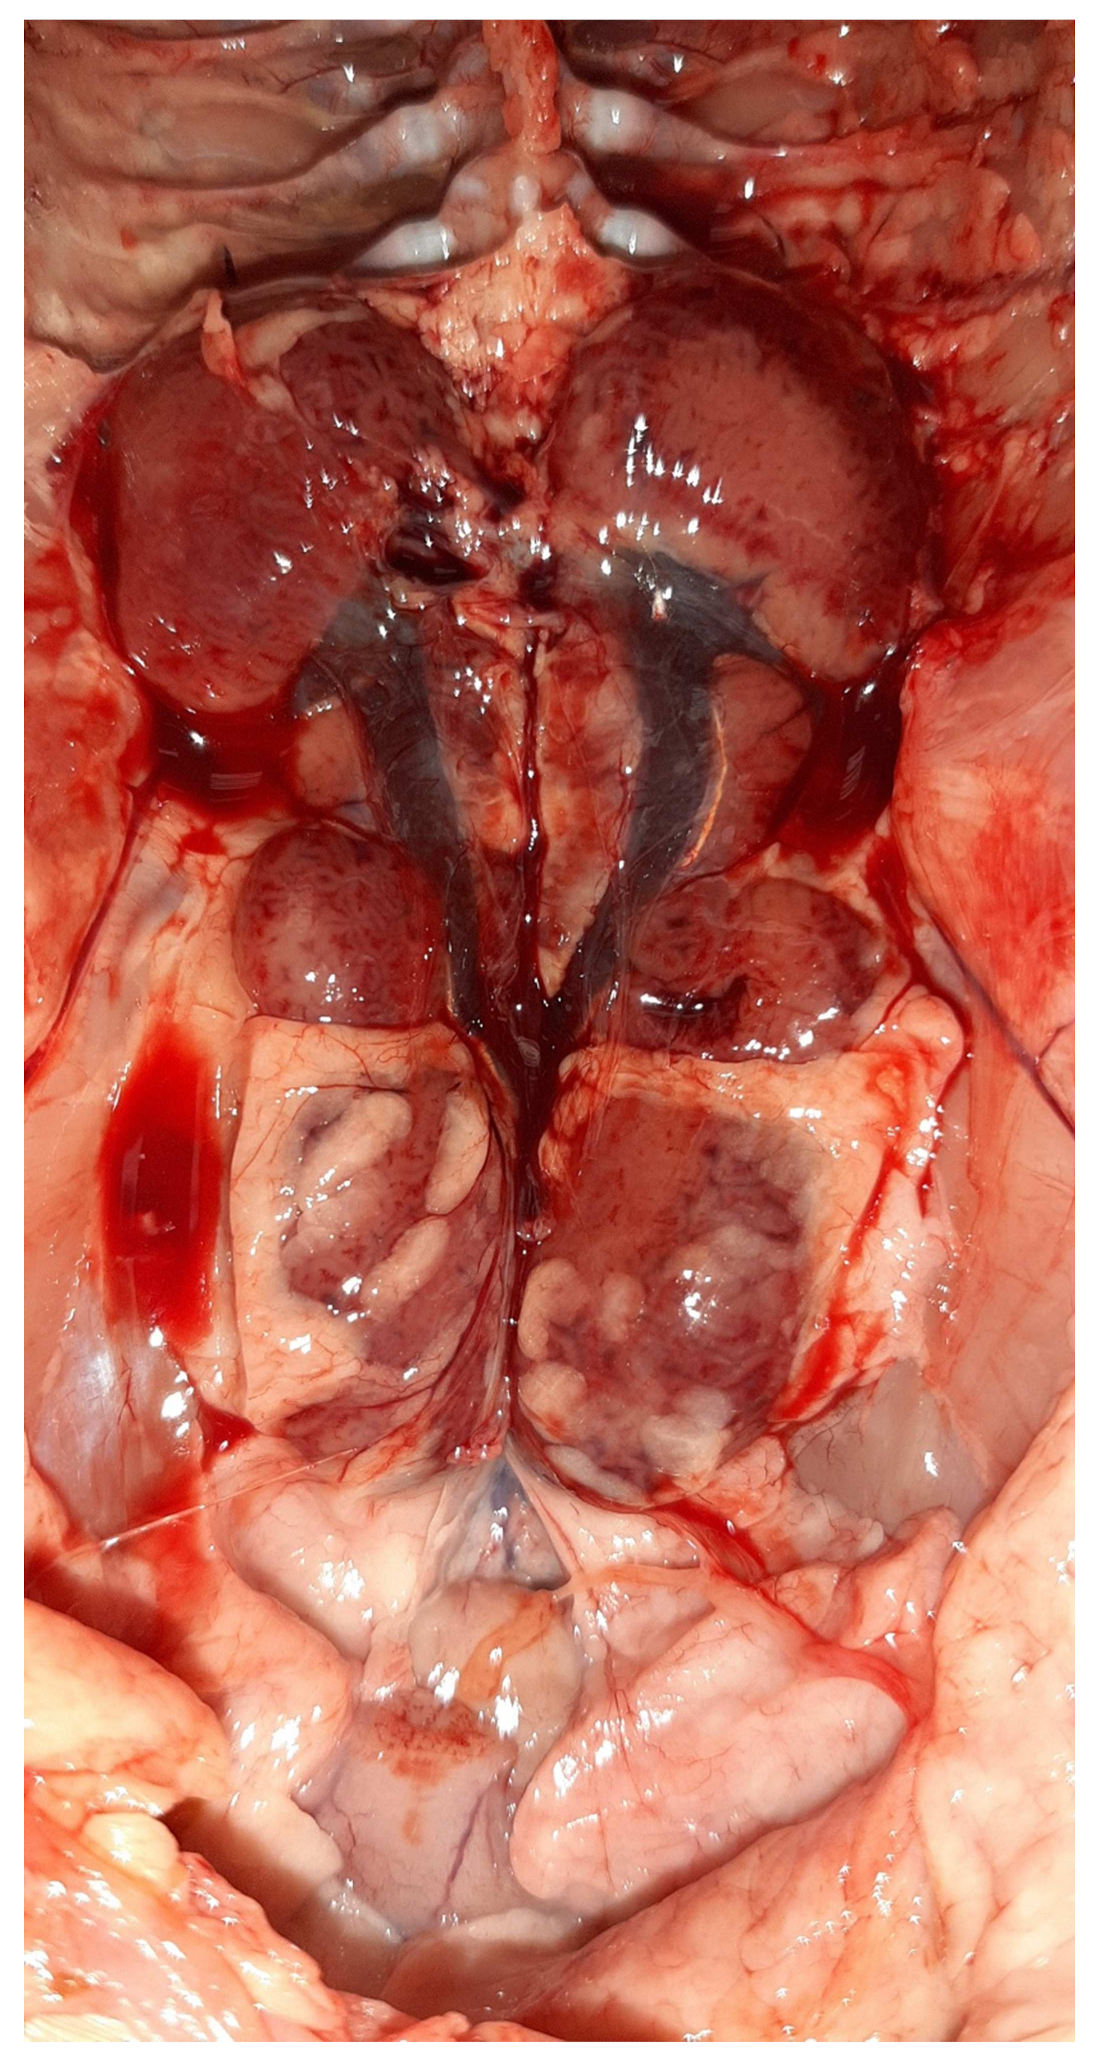

3.2. Postmortem Examination

3.5. Histopathology